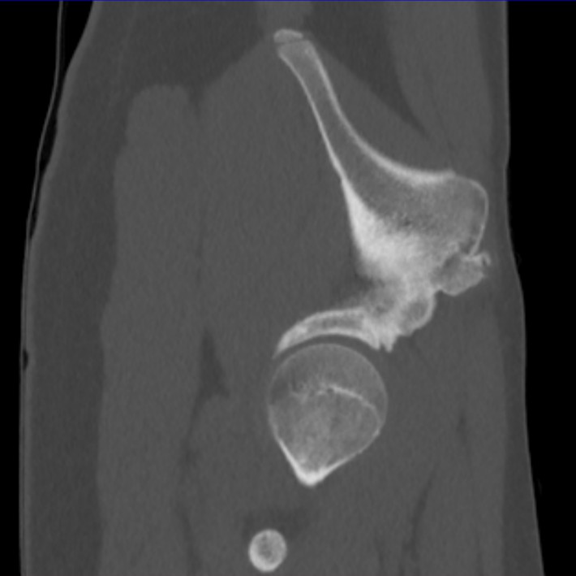

Standard pelvic radiography revealed a displaced bony fragment at the right AIIS. CT scan confirmed the avulsion fracture without intra-articular involvement or adjacent soft tissue injury.

During follow-up, a spontaneous snapping was noted at the AIIS during activity, associated with mild bony hypertrophy at the avulsion site, confirmed on CT and MRI. No persistent pain or joint impingement was observed. The bony hypertrophy represented an adaptive consolidation response and did not impair functional recovery (Figures 1-6).

Figure 2. CT scan initial axial slice: EIAI avulsion.

Figure 5. Pelvic CT scan at 6 months post-traumatic.

Figure 6. Pelvic CT scan at 6 months post-traumatic.